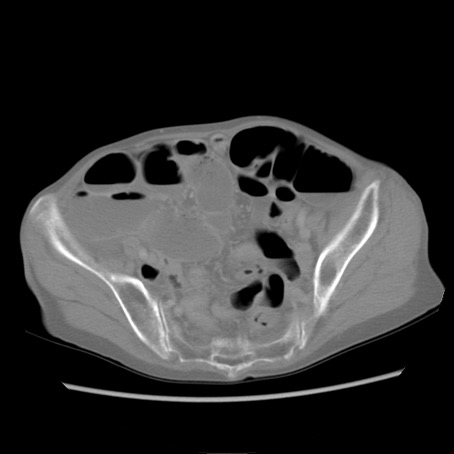

冠状断像